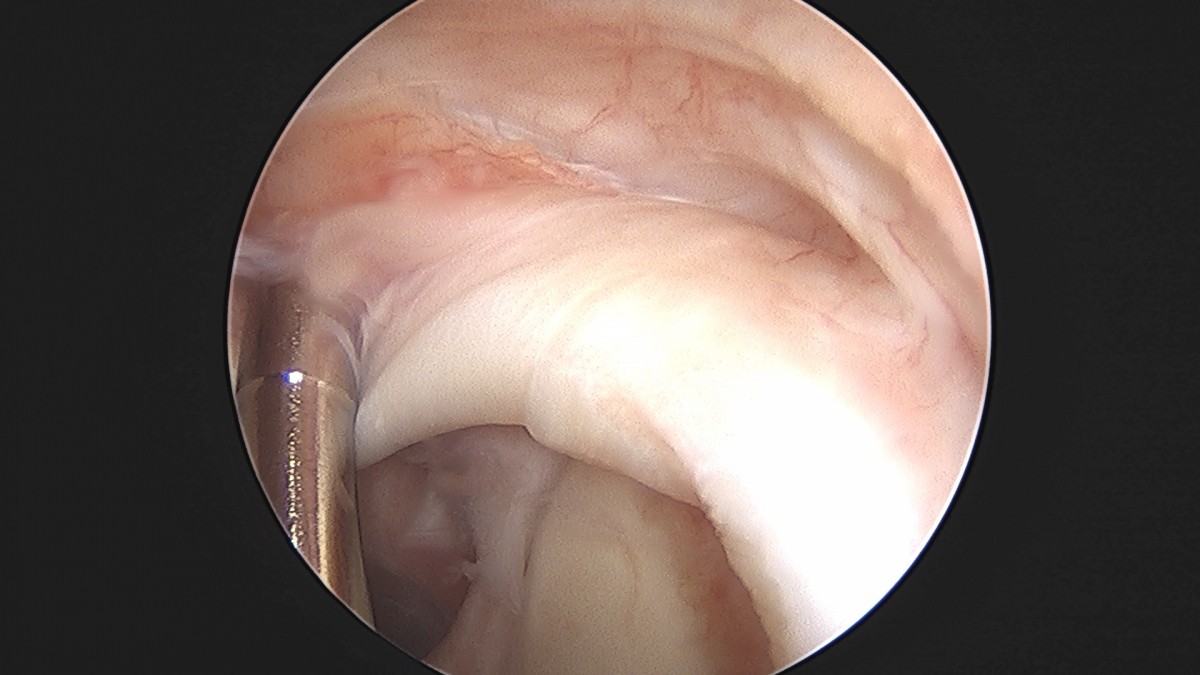

정지영원장님 어깨 관절낭 이완술 이상O 환자

dae765e4d9ac96aee867c9d6292d8784_1758009479_911.jpg